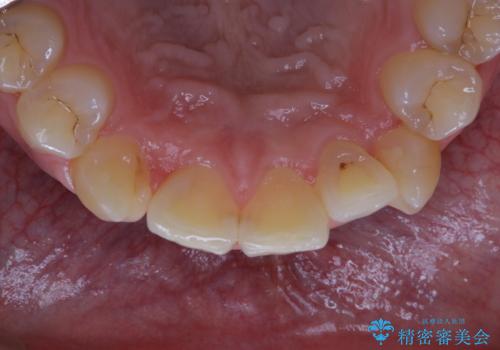

前歯メインにステインの付着が見られ、コース内容を相談した結果PMTC(保険外治療)の30分コースを行いました。